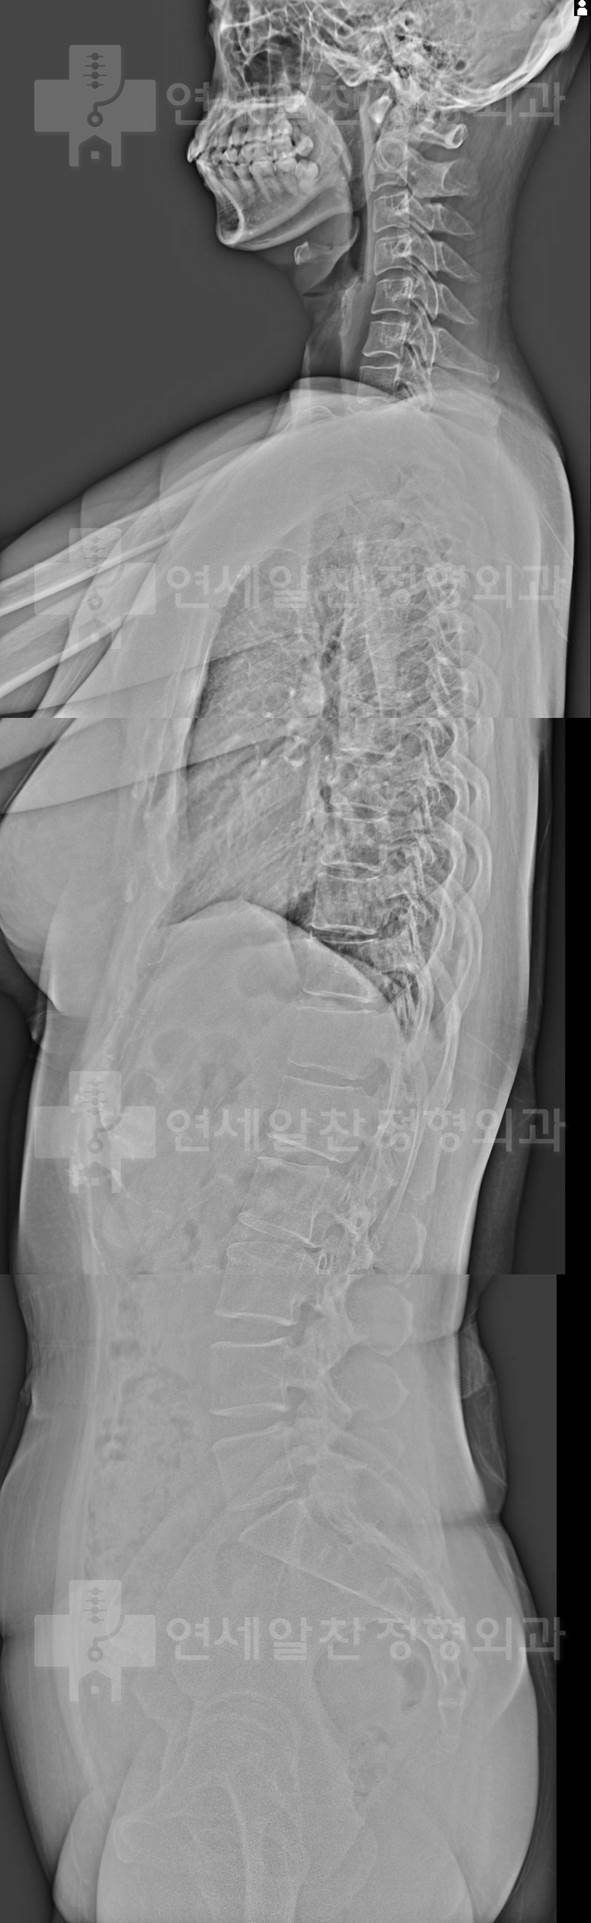

어깨의 가동범위 확보를 위해서는 물론 어깨 관절 자체의 문제만 해결해도 좋아지는 경우들이 많다. 하지만 흉추의 문제 또는 경추의 문제로 인한 기능부전이 동반되었을 경우 치료가 잘 되지 않는 경우들이 있다. 이 환자의 경우도 전체적인 사진에서 관찰해 보면

척추의 전만, 후만이 형성되지 않고 straight spine을 보인다. 특히 흉추의 후반이 소실되어 흉추의 가동성 확보가 되지 않아 견갑골의 안정성 및 움직임에 문제가 있을 가능성이 아주 많은 상태로 이에 대한 재활을 시행하였다. 외국에서 거주하는 사정으로 homework 위주로 진행하였으며 외국에서도 재활치료 병행을 권고하였다. 고맙게도 3개월 뒤 다시 본원을 내원하여 경과 관찰을 할 수 있었다. 환자는 통증 및 가동범위가 많이 개선되었다고 하였다.